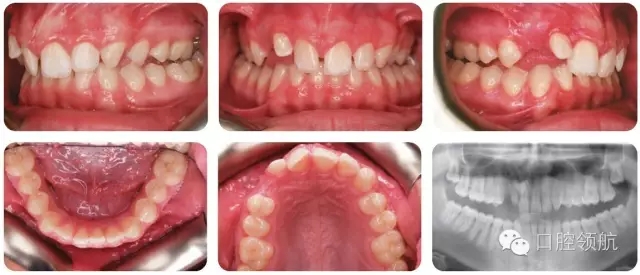

12歲的男性患者,因UR2異位轉(zhuǎn)診至正畸醫(yī)生處治療。

該患者錯(cuò)牙合特點(diǎn)(圖2.38)是什么?

● II類2分類切牙關(guān)系。

● 覆牙合較深。

● 中線不調(diào)(上中線右偏2mm)。

● 后牙近中尖對(duì)尖關(guān)系(雙側(cè))。

● 上牙弓中度擁擠。

● UR3未萌,可能與UR2異位。